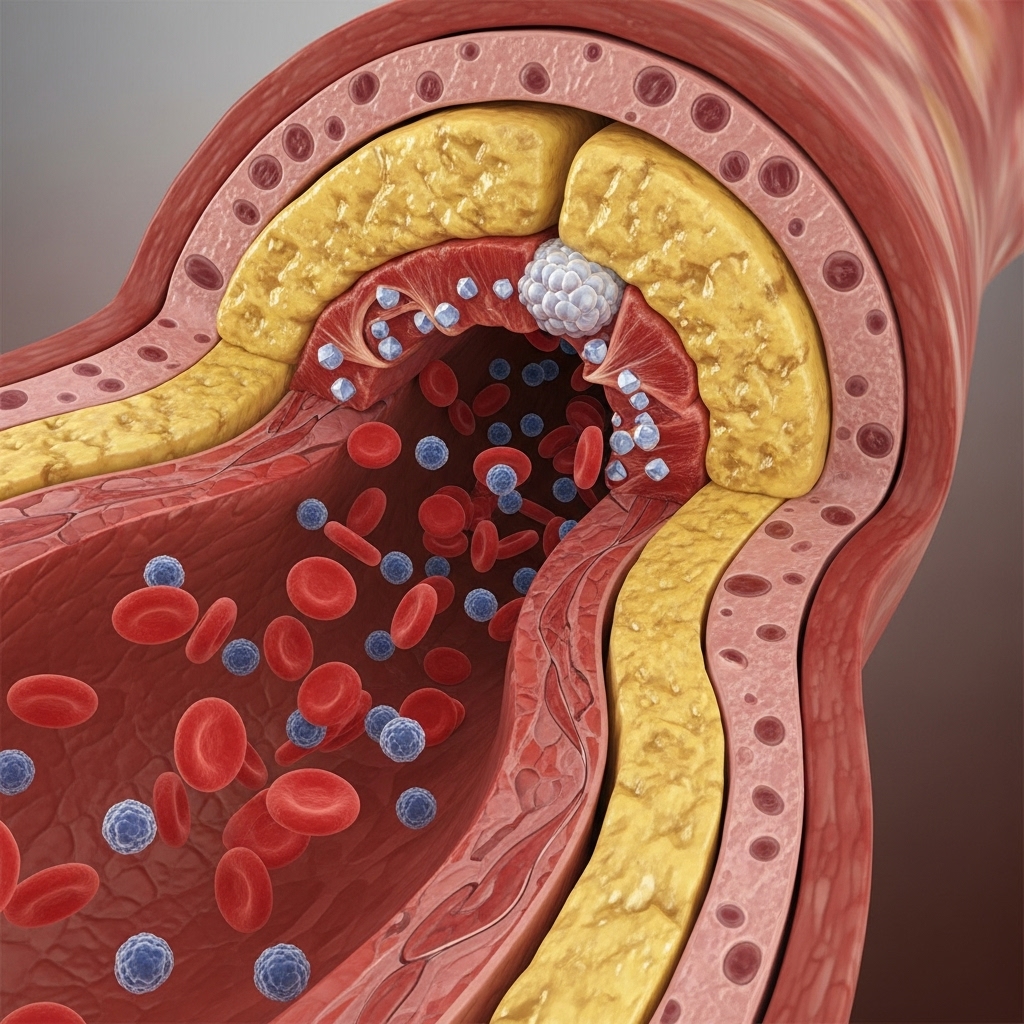

Chronic Limb-Threatening Ischemia (CLTI) is the most severe form of Peripheral Artery Disease (PAD). It occurs when there is a significant blockage in the arteries of the lower limbs, drastically reducing blood flow. This condition can lead to severe pain, non-healing wounds, and, if left untreated, may require amputation. Timely diagnosis and intervention are critical to saving limbs and improving patient outcomes.

CLTI is primarily caused by atherosclerosis, a condition where plaque builds up inside the arteries, narrowing and hardening them. Key risk factors that contribute to this condition include: